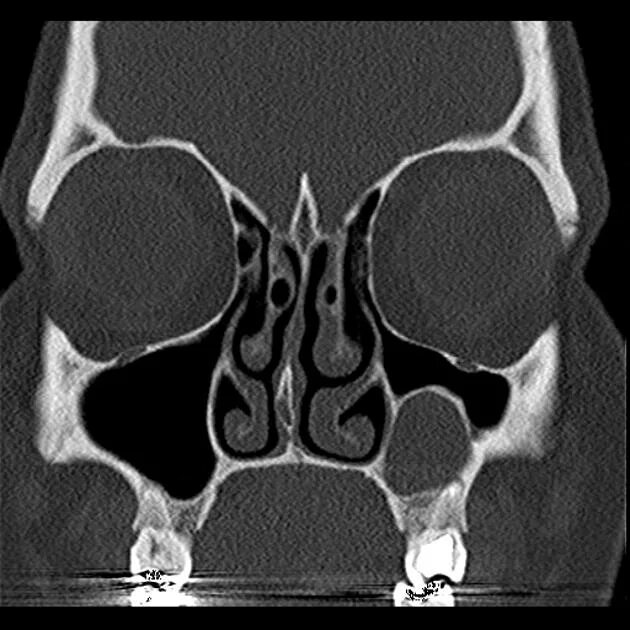

Синусит на кт